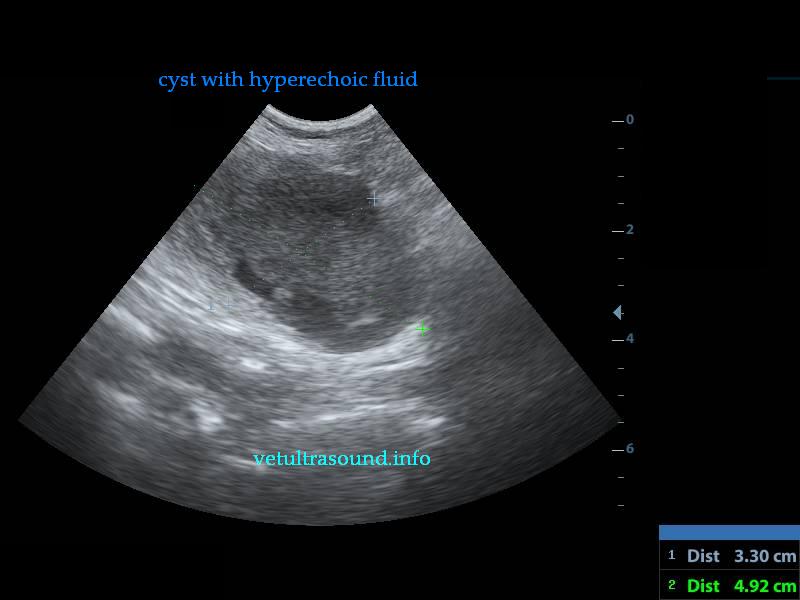

Findings: There was a mild enlargement of the mesenteric lymphnodes(pic3). In a small segment of the small intestine a cyst was noted which was attached to the intestinal wall(pic2.3). There were also dilated intestinal loops before the cyst due to the narrowed intestinal lumen. No free fluid was noted. There was a mild increase of the mesenteric fat arround the cyst.

Ευρήματα: Στην υπερηχοτομογραφική εξέταση της κοιλίας βρέθηκε ήπια διόγκωση των μεσεντέριων λεμφαδένων με αντιδραστική ηχομορφολογία (pic3). Σε τμήμα του λεπτού εντέρου βρέθηκε κύστη με υπερηχογενές περιεχόμενο(pic2) η οποία εφαπτόταν στο τοίχωμά του (pic3)και μείωνε τον αυλό του. Υπήρχε διάταση των εντερικών ελίκων πριν από την κύστη αυτή. Δεν βρέθηκε ασκιτικό υγρό. Το μεσεντέριο λίπος περιφερικά αυτής ήταν υπερηχογενές.